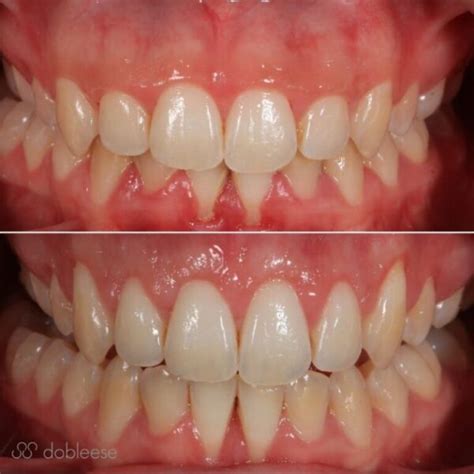

Injerto de encías: Antes y después

Etapas de evolución de un injerto de encía

Si te has sometido a un injerto de encía, es útil conocer las etapas de recuperación:

- Recuperación tras un injerto de encía: La cicatrización del injerto de encía tarda unos 3 meses. Pero lo habitual es que las molestias más importantes desaparezcan tras cinco o siete días, y que luego comience a formarse una nueva encía a partir del injerto.